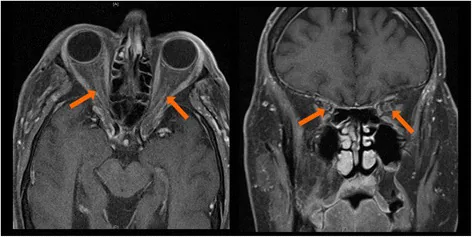

- MRI:眼窩筋炎では眼外筋腫大・造影増強、眼窩脂肪の炎症性変化を描出2)

ICI関連眼irAEは多彩な既知の眼疾患を模倣する。前部ぶどう膜炎では感染性・非感染性ぶどう膜炎との鑑別が必要である。VKH様反応は原発性VKHと臨床的に類似するが、メラノーマに対するICI使用歴が重要な手がかりとなる1)。眼窩筋炎では甲状腺眼症・IgG4関連疾患・特発性眼窩炎症との鑑別を要する2)。

Section titled “眼窩炎症の機序”抗CTLA-4阻害薬(イピリムマブ)が最も高頻度に眼窩炎症を引き起こす2)。抗PD-1/PD-L1阻害薬でも同様の臨床像が報告されている2)。MRIでは眼外筋の腫大・造影増強と眼窩脂肪の炎症性変化を認め、両側性に出現する傾向がある2)。